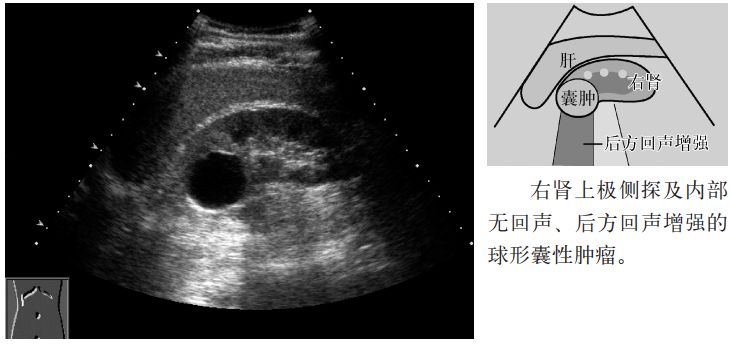

图1 肾囊肿

(1)呈境界清晰的球形肿瘤,内部呈无回声,后方回声增强。

(2)位于皮质内或向皮质外突出。

(3)囊肿壁薄均匀,有时也伴有隔膜。

(4)囊肿壁有时伴有钙化。

(5)如果囊内出血或感染,内部即伴有回声(complicated cyst)。